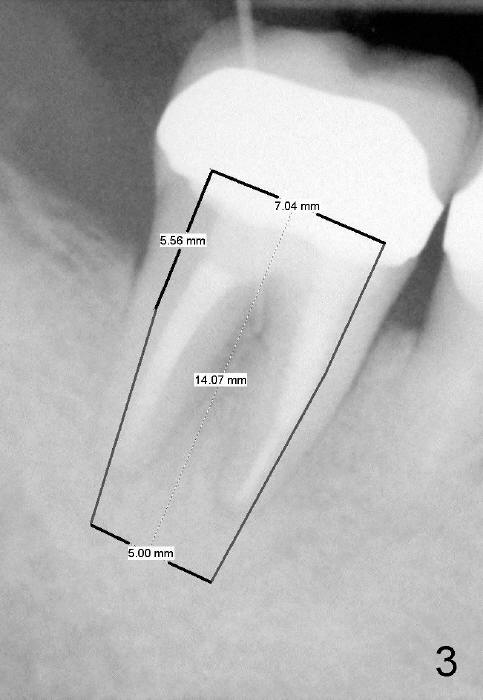

A 51-year-old man has experienced pain and swelling in the lower right 2nd molar for 7 months (Fig.1, P: post in the mesial root; <: gutta percha inserted into a buccal fistula). Fig.2 is taken immediately before extraction (<: purulent discharge from the mesiobuccal fistula) and immediate implant (Fig.3 implant design: 7x14 mm). A vertical root fracture is noted in the mesial root (Fig.4: lingual view). The septum is in fact absent, as compared to Fig.1. The mesiobuccal plate is low; the osteotomy starts lingual to the center of the socket. Fig.5 shows a 4.5x17 mm tap in place: approximately 3.5 mm in the new bone (~2.5 mm from the inferior alveolar canal). When a 7x17 mm tap (14 mm from the gingival margin) is placed in the socket, it looks relatively small. Fig.6 shows a 8x14 mm implant in place with a small gap distally. Mineralized cancellous allograft and Osteogen mixture is placed mainly buccally, followed by a thin strip of collagen dressing and sutures (Fig.7); an abutment (A) is placed to keep perio dressing in place. The perio dressing does not stay long. The buccal portion dislodges by itself 5 days postop. The lingual portion is removed in clinic. New dressing is going to be re-applied, because the buccal wound has not completely healed (Fig.8 <, albeit asymptomatic) with partial exposure of the bone graft (*). Why is the dressing lost so early? The abutment is not long enough; there is plenty of occlusal clearance (Fig.9 arrows). A longer abutment is used to increase mechanical retention for perio dressing (Fig.10). By the time the second perio dressing dislodges, the wound has healed (Fig.11, 13 days postop).